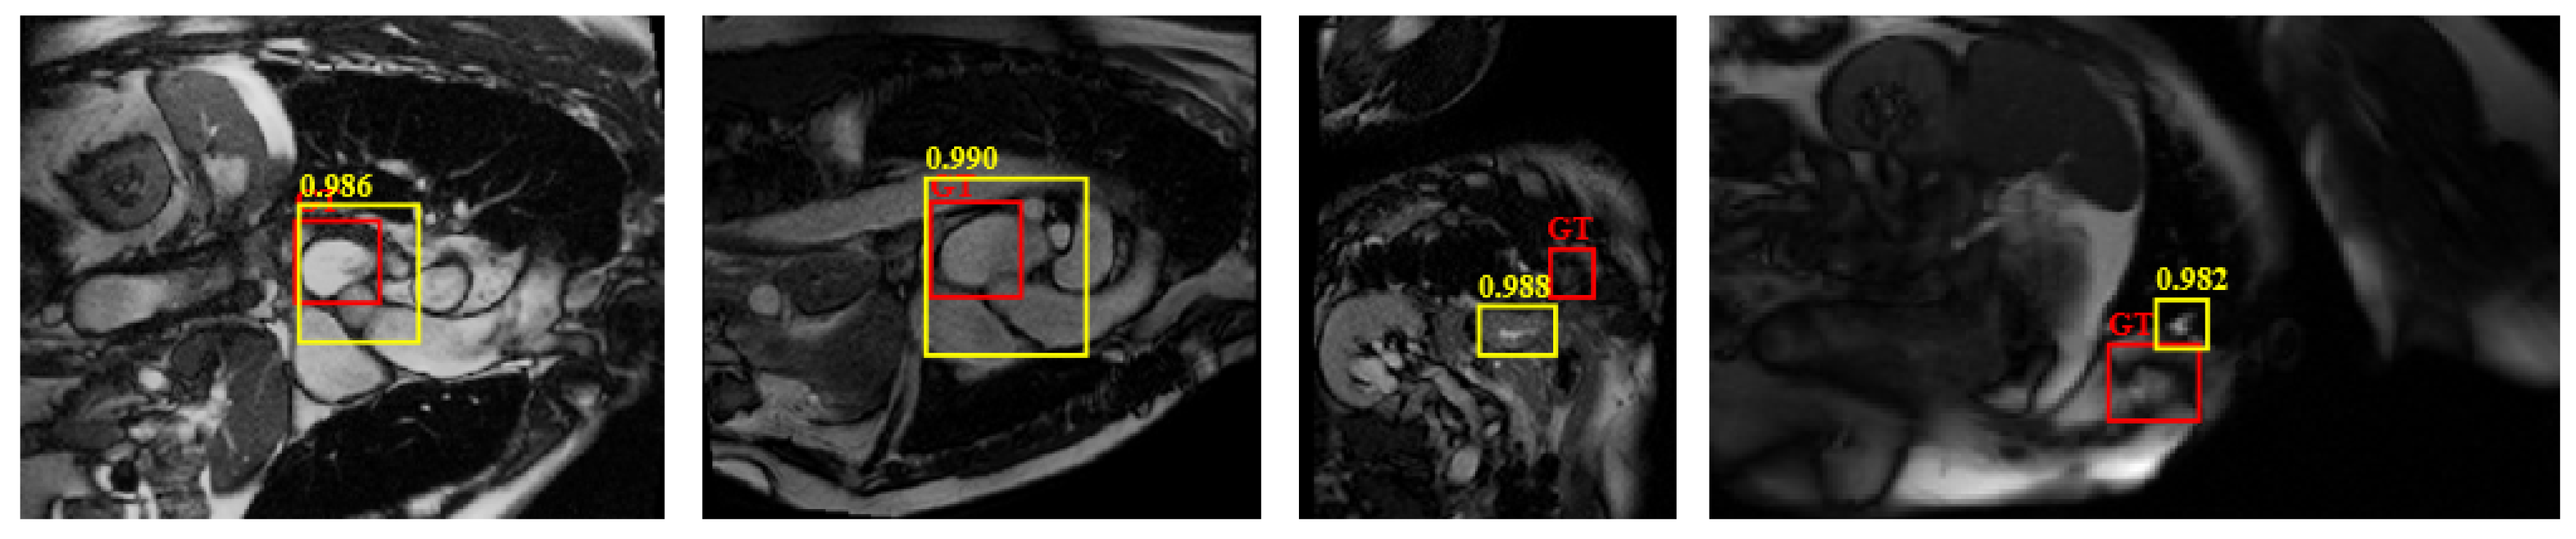

4.3. Comparison with Related Methods

4.4.1. Detection Performance